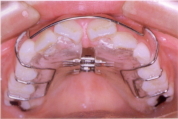

○クウォードへリックス・リンガルアーチ

主に内側から歯を押して必要なスペースを作ります。太いワイヤーの弾力で歯を動かす力を発揮します。